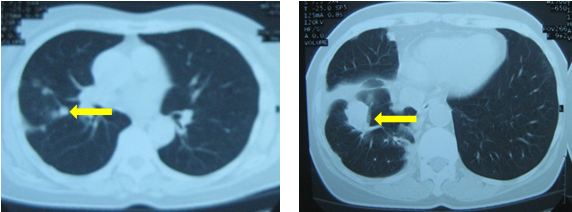

CT lồng ngực (12/12/011)

Hình 3: Hình ảnh chụp CT lồng ngực - u thùy dưới phổi phải: 28× 25mm, kèm theo nốt mờ nhỏ xung quanh